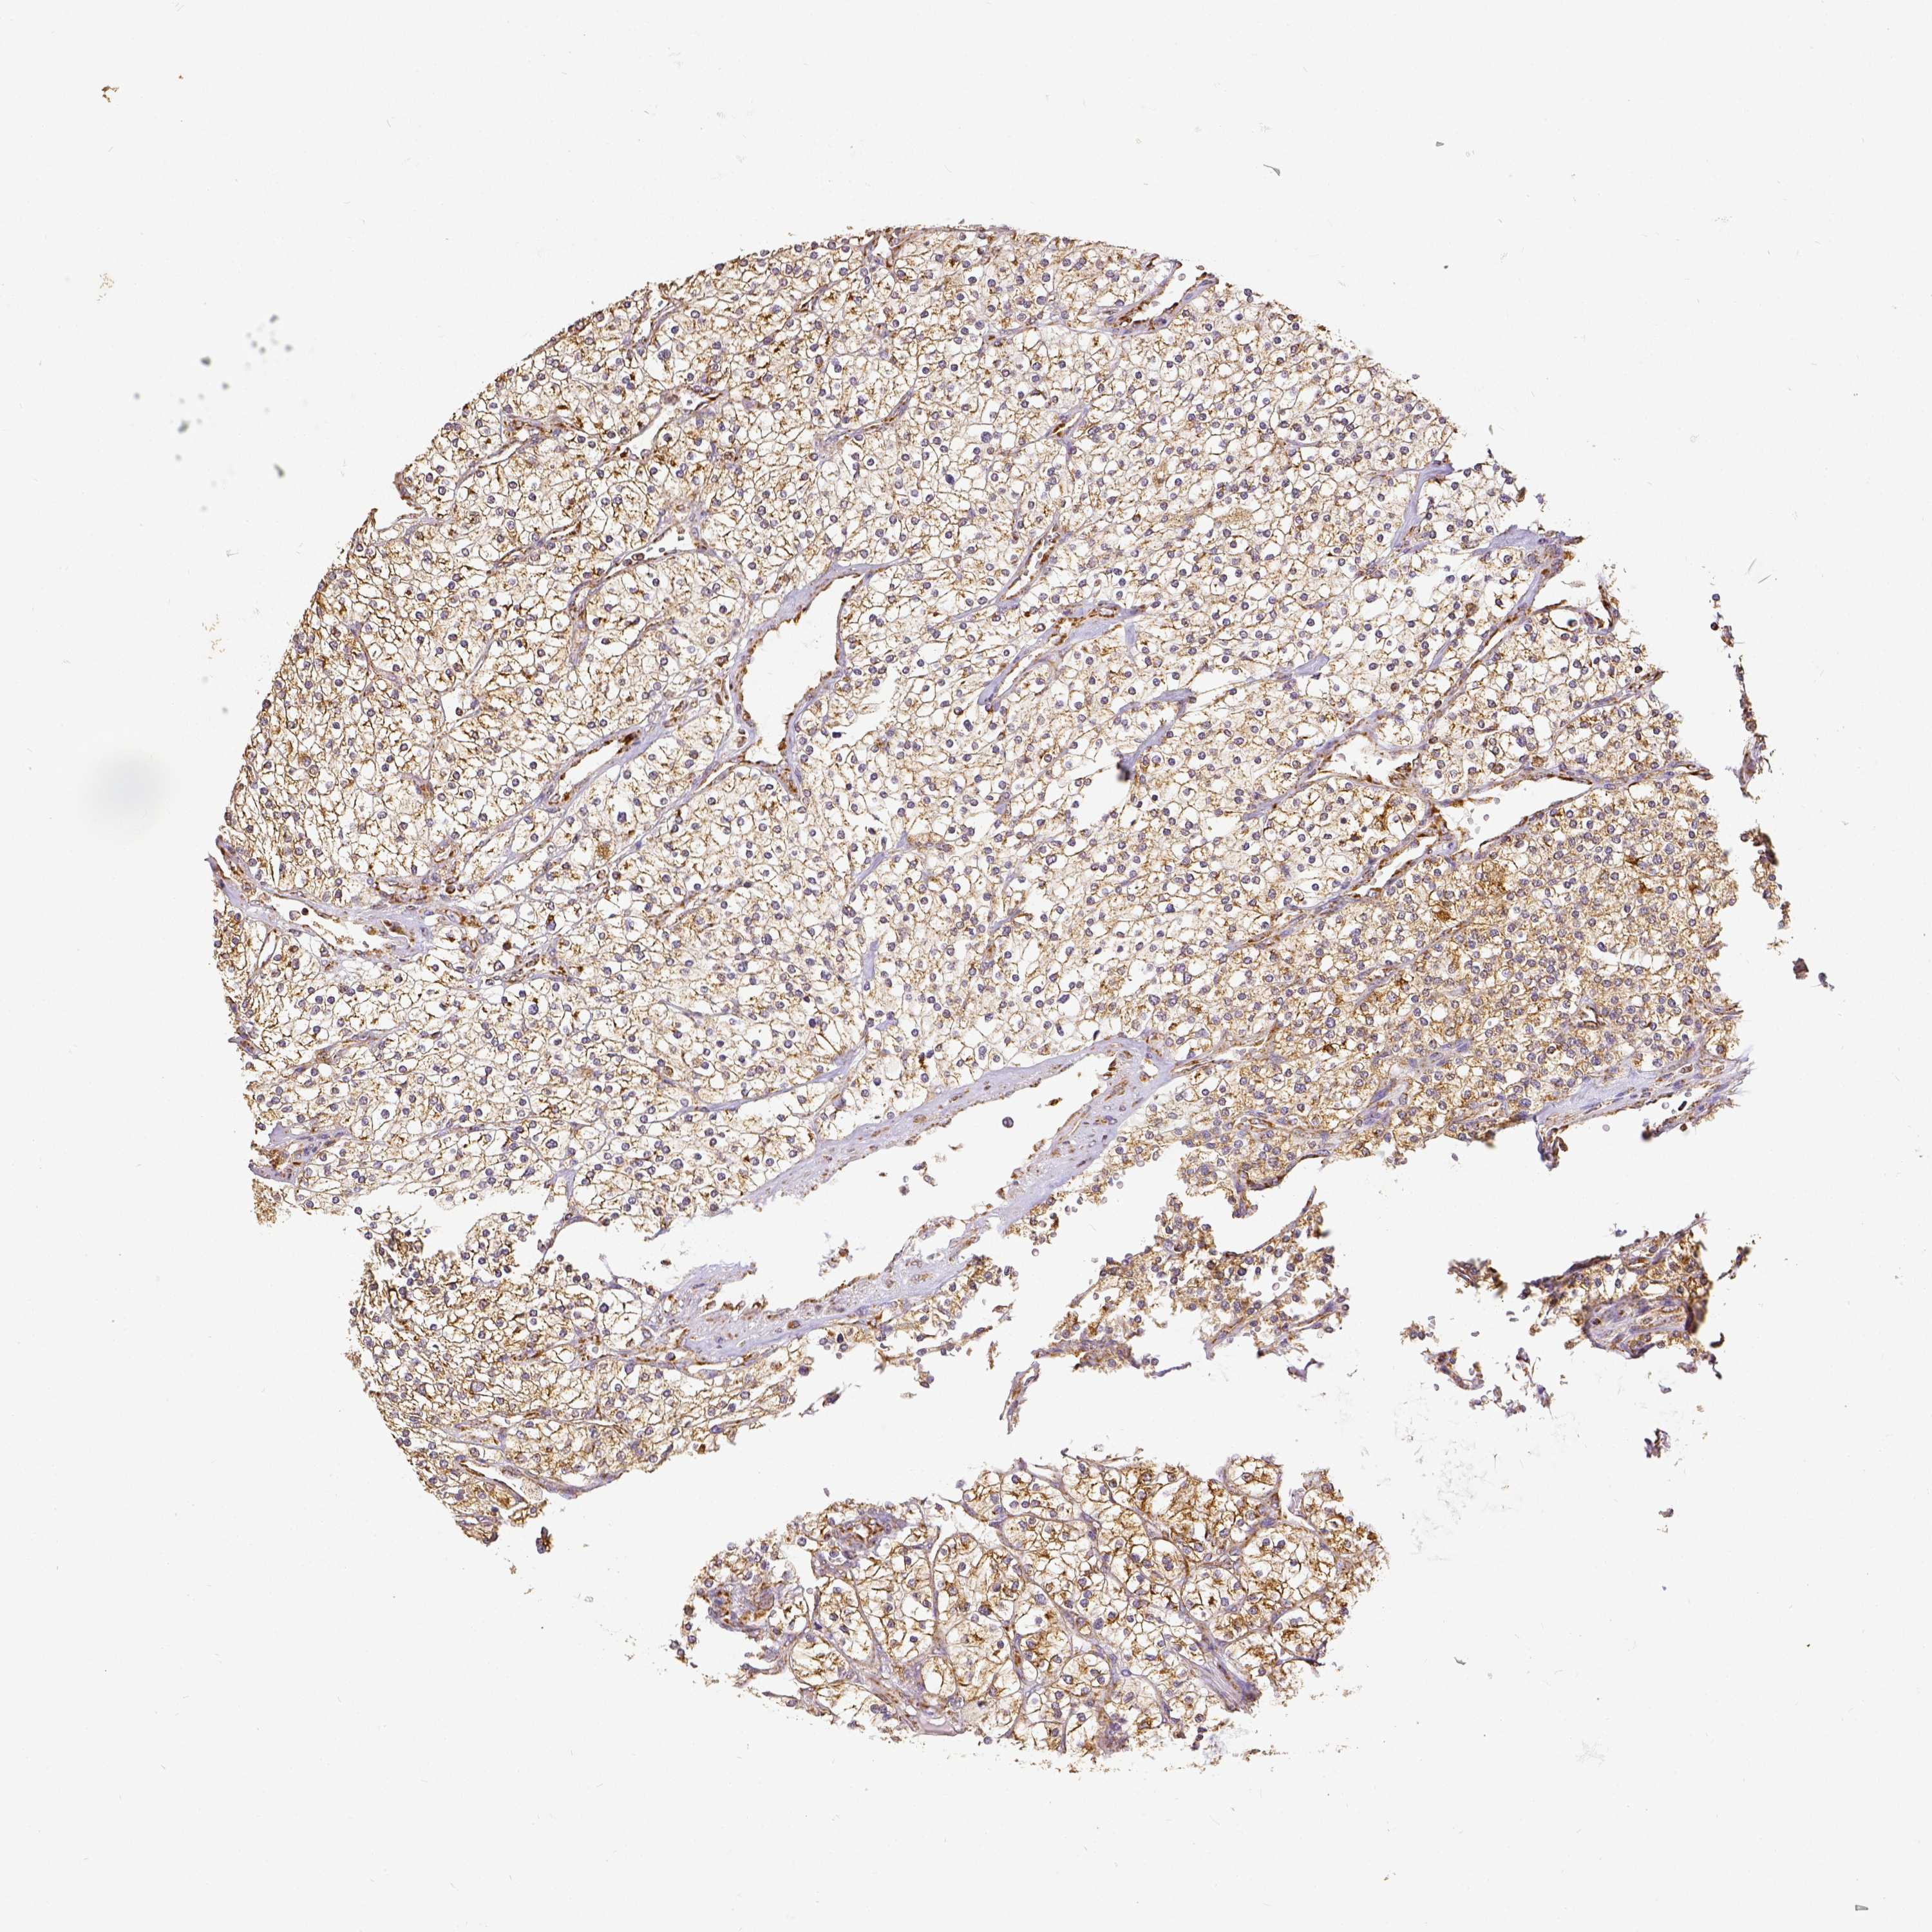

CANCER RENAL CANCER Show tissue menu

KICH TCGA KIRC TCGA KIRC VALIDATION KIRP TCGA PROTEIN RCC CPTAC PROTEIN EXPRESSION